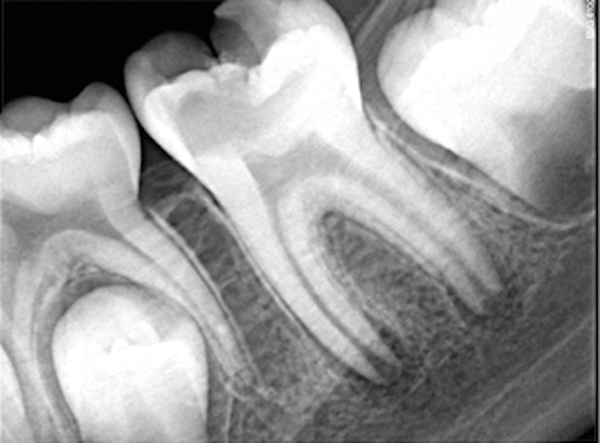

Figure 11. Preoperative radiograph. Courtesy of Dr. Guillaume Jouanny.

Figure 11

Figure 12. Postoperative radiography after full pulpotomy was performed. Courtesy of Dr. Guillaume Jouanny.

Figure 12

Figure 13. Tooth was asymptomatic at 1-year follow-up. Courtesy of Dr. Guillaume Jouanny.

Figure 13

Figure 14. Contralateral tooth at 1-year follow-up. Courtesy of Dr. Guillaume Jouanny.

Figure 14